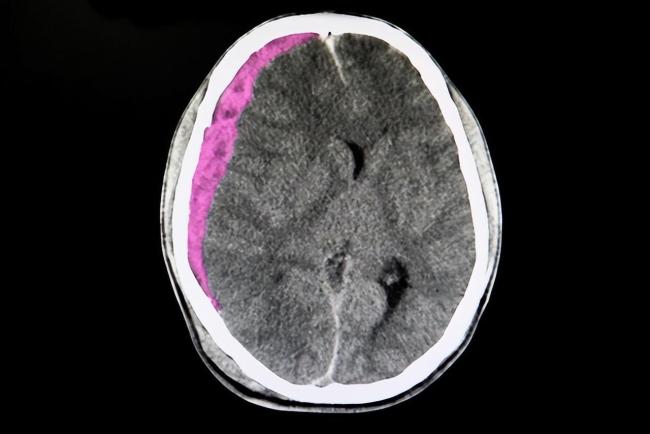

从图片中我们可以看到,该学生头部夸张的呈现出一边高一边低的形状,实在是难以想象孩子受到了什么待遇,也难以想象老师为何下此重手。

据医院诊断证明可以看出,男孩如今确实只有9岁,入院原因是“外伤后头部血肿穿刺2天”。

而且伴随着其他一些如右额顶头发肿胀、伴有压痛等症状。

但万幸的是,除却这些症状外,男孩的其他方面一切正常。

医院的诊断结果是头皮血肿(帽冠腱膜下右侧),而男孩也在住院4天后,成功出院。

医嘱里有重点提及,要定期在神经外科门诊复诊。